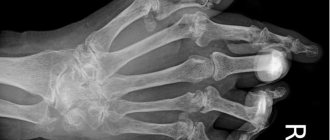

По своему внешнему виду кистозные образования напоминают круглую шишку, величина которой может колебаться от 0,5 до 3 сантиметров. Она обычно подвижна, не имеет соединения с кожным покровом. В некоторых случаях величина диаметра шишки может достигать 5 сантиметров. Скорость роста гигромы индивидуальна. Иногда она растет очень быстро, а порой может оставаться постоянной месяцы и даже годы. Кожный покров чаще всего имеет обычный цвет и вид, но иногда наблюдается его ороговение и небольшое шелушение.

Диагностика гигромы и лечение гигромы

Любая опухоль вызывает обеспокоенность. Это касается и гигромы. Несмотря на то, что она не представляет опасности для организма, необходимо дифференцировать ее с другими новообразованиями. Поэтому должна проводиться комплексная диагностика, в которую входят рентген, УЗИ, КТ, как самой гигромы, так и близлежащих тканей.

Наиболее точный диагноз дает гистология жидкого содержимого образования. Для этого берут пункцию, а внутрь вводится гормональный препарат дипросан. В случае инфицирования применяются антибиотики.

Диагноз выставляется на основании анамнестических данных и характерных симптомов. Но обязательно проводится рентгенография для исключения сопутствующего артроза, артрита, бурсита, синовита. Если у врача возникают сомнения при выставлении окончательного диагноза, то назначаются другие инструментальные исследования:

• УЗИ показано для оценки структуры опухоли, обнаружения в ней жидкости, а в стенках кровеносных сосудов;

• МРТ, КТ проводят при подозрении на образование узлов, определения структуры стенок и содержимого полости.

Выполняется дифференциация гигромы, образовавшейся в области ладони, с опухолями, которые формируются на хрящевых и костных тканях. Также при проведении исследований исключаются липомы, атеромы, эпителиальные травматические кисты. В некоторых случаях с помощью пункции из опухоли извлекается жидкость для изучения ее содержимого.